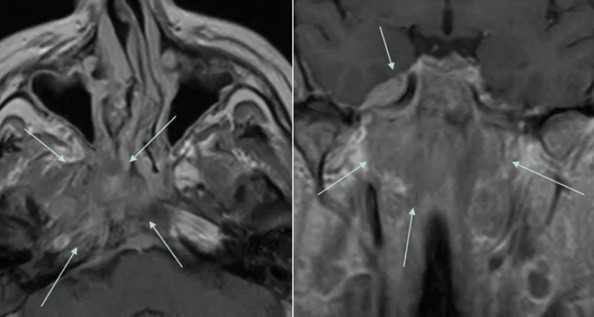

Рис. 10. А. Пациент Е., 52 года. МРТ полости рта, ротоглотки в аксиальной проекции, Т1-ВИ. Опухоль языка небольших размеров, границы визуализируются с трудом за счет перифокального отека (стрелки); В. Тот же пациент. МРТ в аксиальной проекции, Т2 с подавлением сигнала от жировой ткани. Визуализируются границы опухолевого узла, размеры опухоли языка четко определяются (стрелки)

Рис. 11: А. МРТ полости рта, ротоглотки в аксиальной проекции. Рецидив опухоли языка размерами 6,0х6,5 см с распространением на дно полости рта, правую боковую стенку ротоглотки (стрелки). Выявляется переход за среднюю линию; В. Тот же больной. МРТ полости рта, ротоглотки в коронарной проекции. Опухолевый узел показан стрелками. Просвет ротоглотки сужен, деформирован. Опухоль имеет низкий сигнал на Т1-ВИ, аналогичный сигналу от окружающих мышц, при этом размеры опухолевого узла, его объемные характеристики позволяют четко отграничить от интактных тканей. Также отмечается структурная неоднородность патологического образования за счет некроза